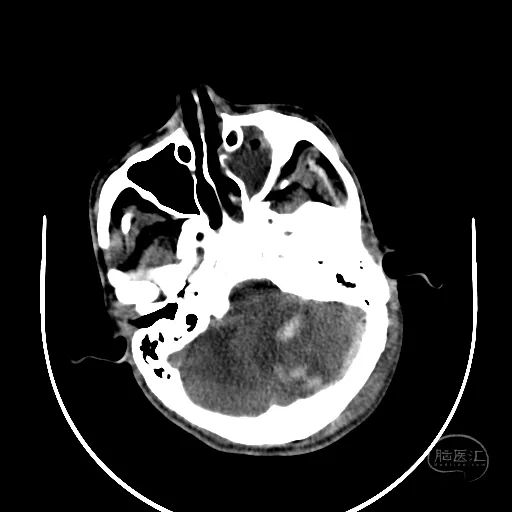

术后第一天复查CT显示后颅窝血肿清除,第四脑室隐约可见。

患者昏迷状,GCS评分3分,双侧瞳孔等大等圆,直径3mm,对光反射迟钝。

额叶血肿清除后,水肿明显。

额叶残余少量血肿,脑室引流管在位。

骨窗见枕骨大孔开放。术中清理枕骨大孔骨折时,无明显出血。